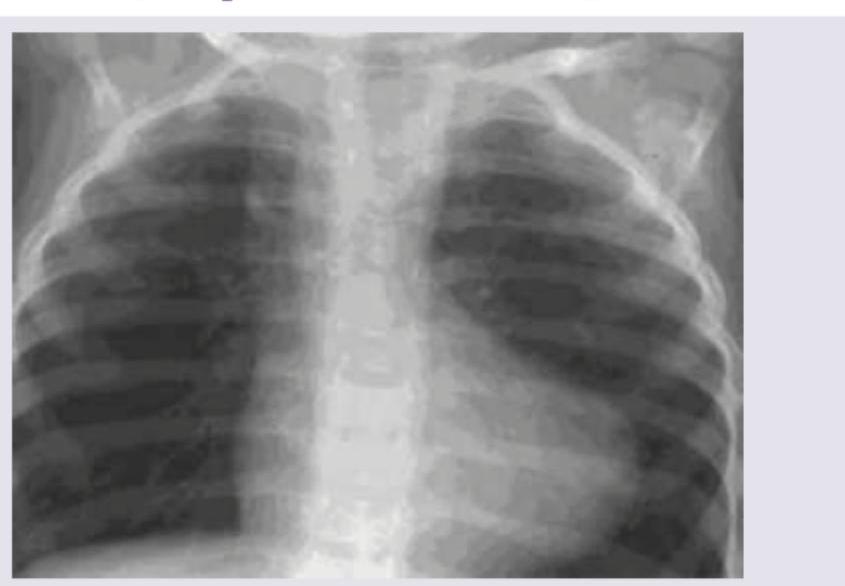

A 1-week-old neonate presents with anoxic spells and single S2. CXR shows all except:

Explanation: ***Pulmonary plethora*** - Pulmonary plethora, or **increased pulmonary vascular markings**, indicates increased blood flow to the lungs, which is not characteristic of Tetralogy of Fallot as it involves **pulmonary outflow obstruction**. - Tetralogy of Fallot leads to **decreased pulmonary blood flow**, resulting in **pulmonary oligemia** (reduced vascular markings) on CXR. *Boot-shaped heart* - This is a classic radiographic finding in **Tetralogy of Fallot** due to **right ventricular hypertrophy** and an upturned cardiac apex caused by **pulmonary hypoplasia**. - The image appears to show early signs of a boot-shaped heart (Coeur en sabot), consistent with the clinical picture of a cyanotic neonate with anoxic spells. *Right-sided aortic arch* - A **right-sided aortic arch** is seen in approximately 25% of patients with Tetralogy of Fallot and is a recognized associated anomaly. - While not universally present, its occurrence is significant enough to be considered a feature of the condition, making it a possible finding. *Right ventricular hypertrophy* - **Right ventricular hypertrophy** is one of the four defining features of **Tetralogy of Fallot** (together with ventricular septal defect, pulmonary stenosis, and an overriding aorta). - While not always directly visible as an enlarged chamber on a CXR, its presence is inferred by the **boot-shaped heart** configuration and the physiological adaptations to pulmonary outflow obstruction.